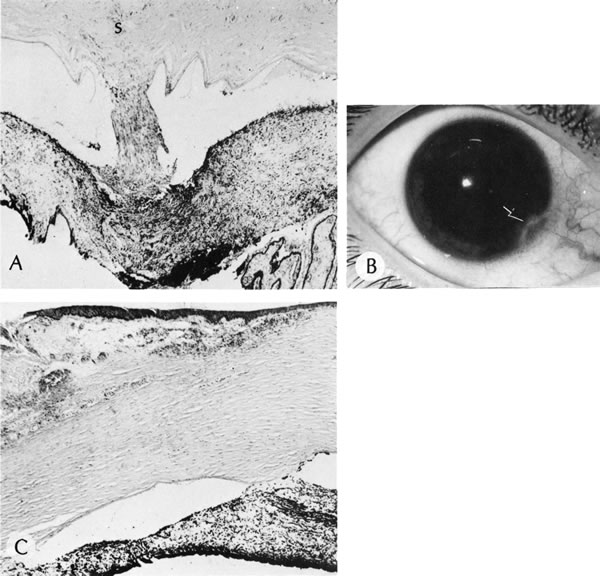

By light microscopy, eosinophilic intranuclear inclusions are characteristic of herpes simplex viral infections and represent the result of viral replication (Cowdri type A inclusions).121 Hypersensitivity type IV reactions in the stroma are characterized by lymphocytic and plasmacytic infiltrates. Intranuclear inclusions are relatively rare and are not found in most specimens. Viral particles occasionally can be found in multinucleated giant cells or within the stroma, especially in keratocytes (Figs. 20 and 21).

Fig. 20. Herpes simplex. A. Typical dendritic ulcer. B. Scanning electron micrograph of a dendritic ulcer in the epithelium of a rabbit cornea. C. Many intranuclear inclusions (arrows) are present in the corneal epithelium near the edge of the ulcer. D. Virus particles (arrows) of herpes simplex are present in the nucleus. E. Virus particles also are present within the cytoplasm. Note the large size of the cytoplasmic virions. Some particles show empty capsids, whereas others are complete, containing nucleoids. (Courtesy of SEI Photoarchives.) (B Courtesy of Dr. R. C. Eagle Jr; C from Font RL: Chronic ulcerative keratitis caused by herpes simplex virus. Arch Ophthalmol 90:382, 1973.)

Fig. 21. Herpes simplex. A. Clinical appearance of bullous keratopathy. B. Chronic condition shows development of bullous keratopathy. The anterior chamber inflammatory reaction contains multinucleated inflammatory giant cells (arrow), shown under high magnification in inset. C. Ulcerated bullous keratopathy (arrows). A corneal abscess (a) and hypopyon (h) are present. Note (inset) the subluxation of the lens to left, caused by the loss of zonula-lens attachments on the right, resulting in a “blunted” appearance of the right side of the lens. (Courtesy of SEI Photoarchives.)